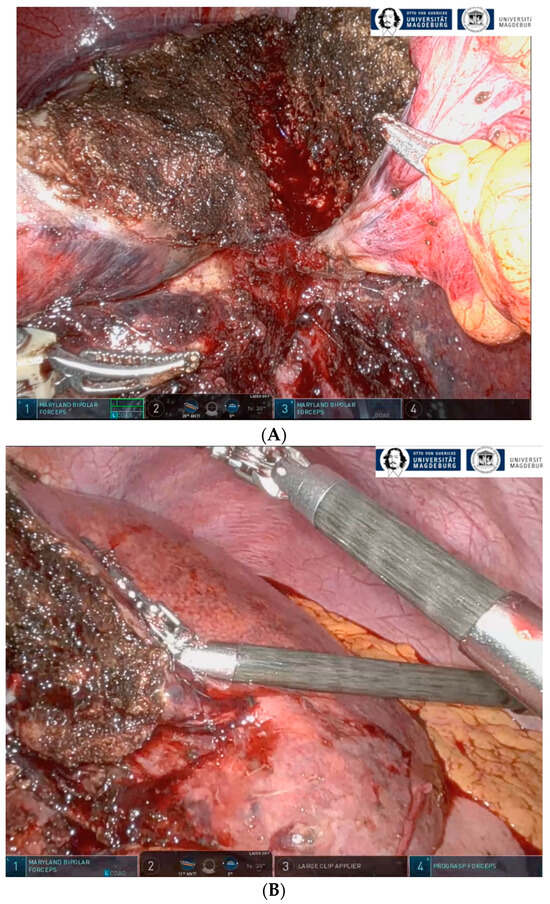

2.3. Technique of rALPPS

- Perrakis, A.; Rahimli, M.; Gumbs, A.A.; Negrini, V.; Andric, M.; Stockheim, J.; Wex, C.; Lorenz, E.; Arend, J.; Franz, M.; et al. Three-Device (3D) Technique for Liver Parenchyma Dissection in Robotic Liver Surgery. J. Clin. Med. 2021, 10, 5265. [Google Scholar] [CrossRef] [PubMed]